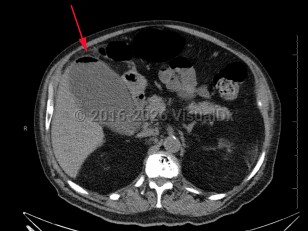

Emphysematous cholecystitis

Emphysematous cholecystitis is a rare variation of acute cholecystitis caused by secondary infection of the gallbladder wall with gas-forming bacteria such as Clostridium welchii, Clostridium perfringens, Escherichia coli, and Bacteroides fragilis as well as Pseudomonas, staphylococci, and streptococci. Men between the ages of 50 and 70 are most frequently affected. Type 2 diabetes and gallstones are common in affected patients. Emphysematous cholecystitis can also arise due to ischemia from atherosclerosis of the cystic artery.

Common presenting symptoms are similar to those for acute cholecystitis and include upper right quadrant abdominal pain, nausea, vomiting, and low-grade fever. On physical exam, abdominal wall crepitus may be palpated in the area overlying the gallbladder. Common complications include gangrene, perforation, pericholecystic abscess, and peritonitis. Uncommon complications include pneumoperitoneum.

Emergent antibiotic therapy followed by cholecystectomy is the treatment of choice due to increased risk of perforation.